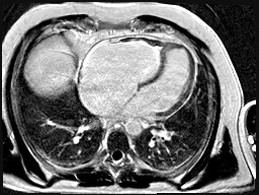

We report the case of a 48-year-old male with chronic eosinophilic leukaemia (CEL) complicated by multiorgan damage, including chronic kidney disease (CKD) and liver disease with recurrent ascites. Cardiac follow-up began at CEL diagnosis. The patient remained stable until 2015, when he underwent two atrial tachycardia ablations. Cardiac magnetic resonance imaging suggested Loeffler endocarditis, showing right ventricle (RV) fibrosis, mildly impaired RV systolic function and severe tricuspid regurgitation (TR). The left ventricle (LV) remained preserved. Cardiac computed tomography excluded coronary disease. In June 2025, despite guideline-directed medical therapy, the patient developed severe dyspnea, massive ascites and acute kidney injury on CKD. Transthoracic (TTE) and transoesophageal echocardiography showed torrential TR not amenable to percutaneous repair. Laboratory results showed normal blood count, serum creatinine 5.5 mg/dL, bilirubin 2 mg/dL, NT-proBNP 7950 pg/mL. Electrocardiography showed junctional rhythm. On admission, intravenous furosemide was continued. A 5-L paracentesis yielded negative cytology and microbiology. TTE confirmed severely dilated RV and atrium, paradoxical septal motion, hypokinetic RV and torrential TR. LV function was normal. Right heart catheterization revealed reduced cardiac index (2.04 L/min/m²), mildly elevated pulmonary capillary wedge pressure (14 mmHg), normal pulmonary pressures (24/15/19 mmHg), normal pulmonary vascular resistance (1.3 WU) and elevated right atrial pressure (19 mmHg). Low dose dopamine (2 mcg/kg/min) improved perfusion and diuresis, leading to clinical stabilization with weight loss (−19 kg), waist reduction (−11 cm), and improved labs. Multisystem evaluation was undertaken. Portal hypertension and decompensated liver disease were excluded. Liver biopsy revealed extensive fibrosis without cirrhosis or malignancy. MELD-XI was 48. Haematology confirmed longstanding CEL remission. Imatinib was discontinued, with monthly molecular monitoring. Renal function normalized under inotropes, with no further tests needed. Extracardiac and serologic workup was negative. Blood type: B Rh+. The case was reviewed by the transplant team. No absolute contraindications to heart transplantation were found. Combined heart–liver transplantation was deemed unnecessary given the absence of cirrhosis. LVAD was excluded. On August 1st, 2025, the patient was listed for urgent heart transplantation (Urgency level 2).